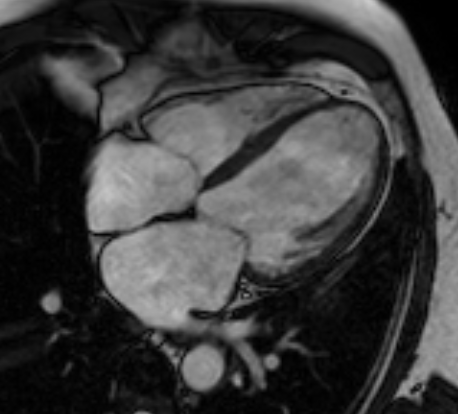

Real scans planned by AID-MR

4 Chamber